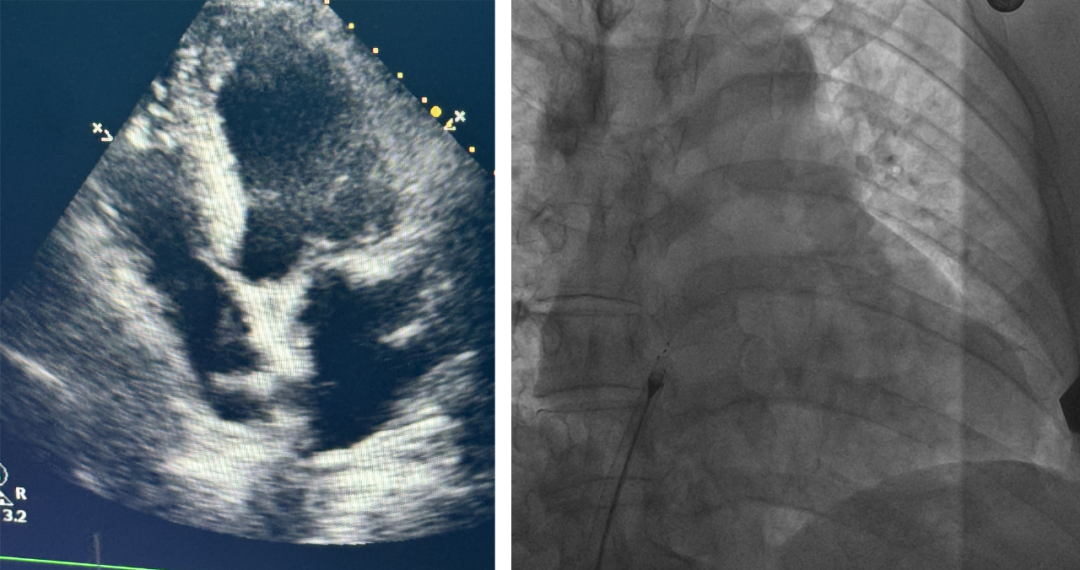

入院后,病区的主治医生武文艺及专家团队通过术前TCD发泡实验与经食道彩超的细致分析,以及精心的检查和评估,最终王先生被确诊为卵圆孔未闭。

手术当天,由心脏中心主任张友恩博士、副主任吴三五博士、吴悠博士等组成的专家团队,携手超声科任润润医生,凭借精湛的技术和默契的配合,成功将生物可降解封堵器植入患者心脏,完美闭合了卵圆孔。